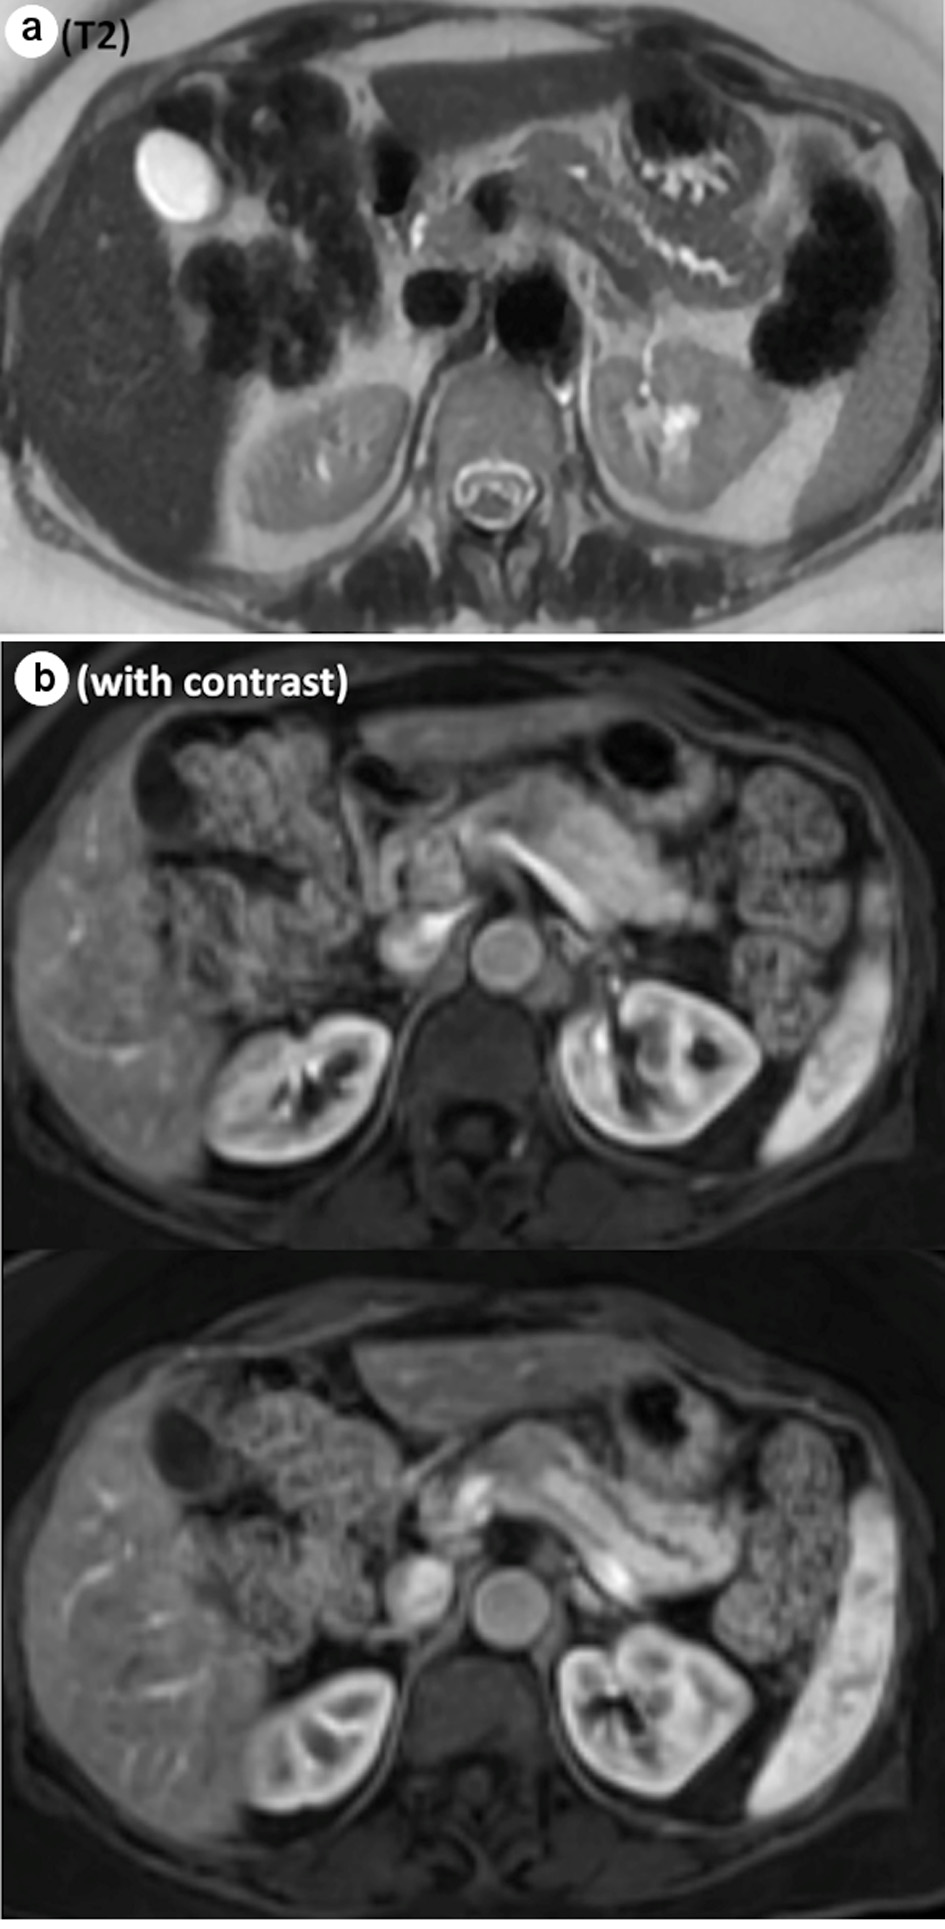

A 62-year-old female without any significant past medical history was referred to the surgical oncology department with a newly identified pancreatic neck mass. It was discovered during her workup of worsening right upper quadrant pain that had been present for several years. The pain was intermittent, stabbing, radiating to her mid back, exacerbated by food and associated with nausea, bloating, constipation and loss of appetite. An abdominal ultrasound demonstrated a hypoechoic lesion in the pancreatic body region measuring 2.2 × 1.8 × 1.9 cm. Subsequent magnetic resonance imaging (MRI) found a hypoenhancing mass in the pancreatic body which was moderate intensity on T2 sequence, measuring 2.4 × 1.9 × 3.2 cm, causing mild upstream dilation of the pancreatic duct in the body and tail (Fig. 1a, b). The lesion abutted the portal confluence and there was no arterial involvement. Interestingly, there was additional downstream pancreatic ductal dilation up to 4 mm and the pancreatic neck was atrophic as well. The cross-sectional imaging findings were highly concerning for pancreatic adenocarcinoma. After discussion in a multidisciplinary tumor board, surgical resection without tissue diagnosis was considered reasonable given the tumor location and distinct imaging characteristics. Neoadjuvant chemotherapy with tissue diagnosis was considered but forgone, as a potential tumor growth during the neoadjuvant treatment would possibly make this tumor unresectable. Her serum carcinoembryonic antigen (CEA), carbohydrate antigen 19-9 (CA19-9) and IgG4 level were within normal limits.

![]() Click for large image | Figure 1. Representative images from MRI. (a) Abrupt cut off of the main pancreatic duct on the T2 sequence. (b) Hypoenhancing mass, measuring 2.4 × 1.9 × 3.2 cm, on the contrast study. MRI: magnetic resonance imaging. |